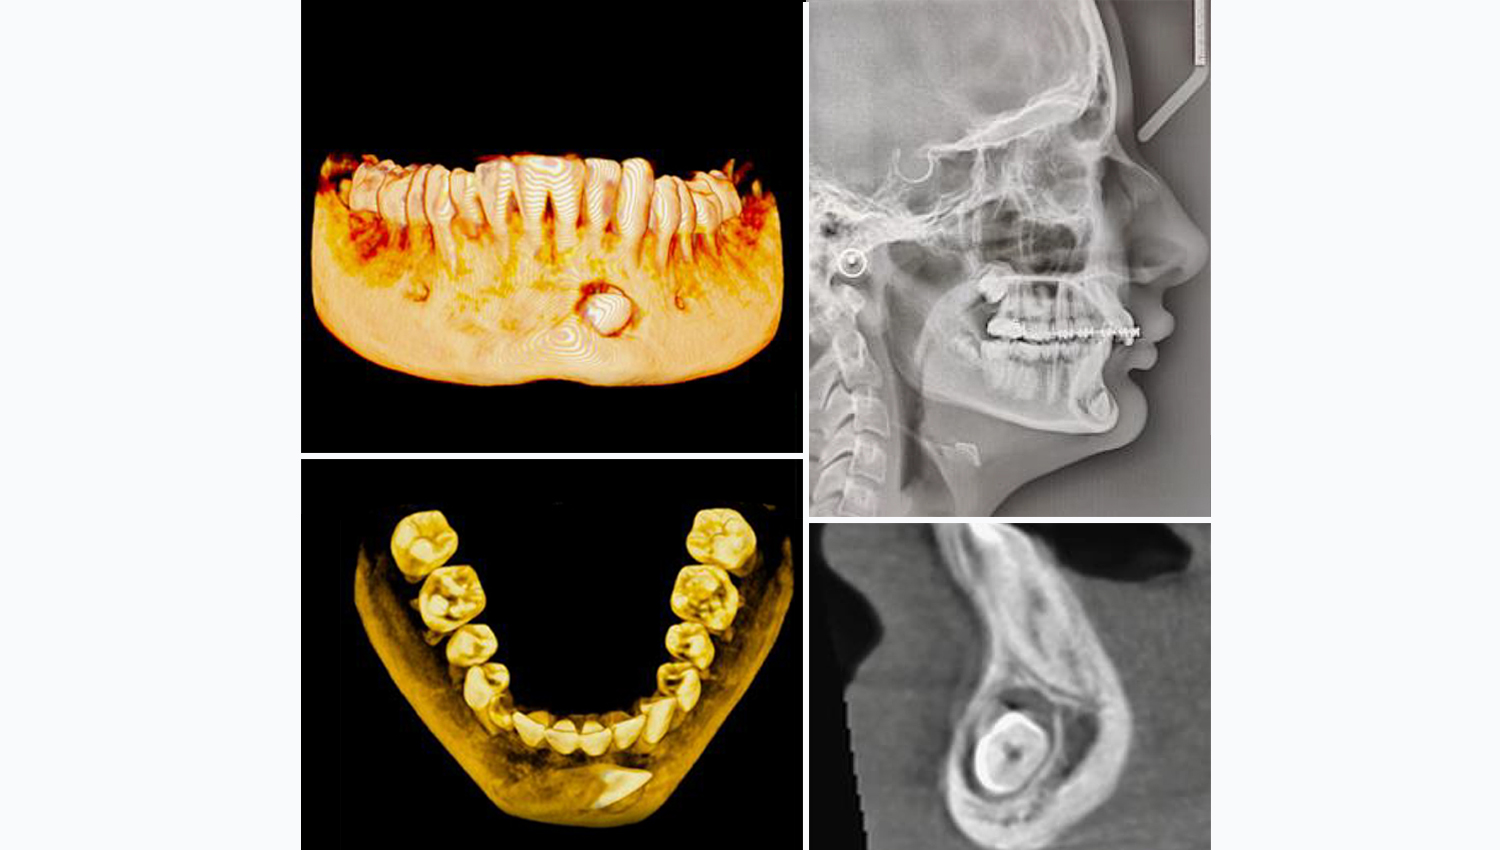

- Impacted 33

1.Horizontally impacted 43. Due to its unfavourable position, the tooth cannot be moved orthodontically.